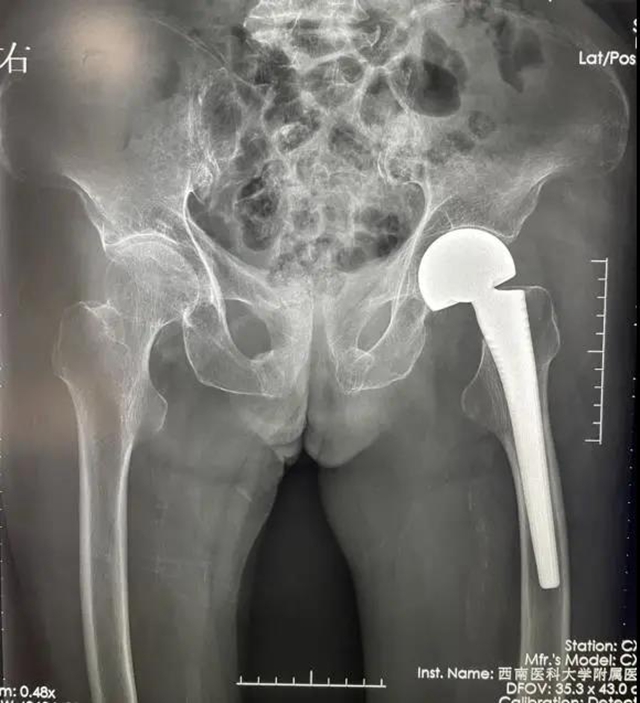

第一次手术,术前X片检查

第一次手术,术后X片检查